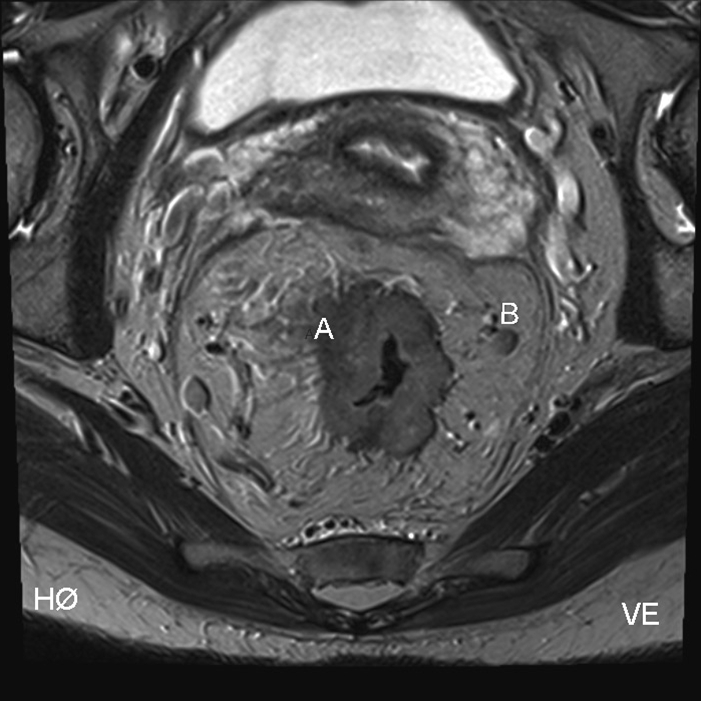

Colorektal cancer, MR, tværsnit

A: Rectumcanceren er vokset helt igennem tarmen (gennemvokset) ved A

B: Malignitetssuspekt lymfeknude ses lige under B'et.

Billedet viser en MR skanning af en rectumcancer i tværsnit. Tumor er stor og beliggende i den øvre del af rectum.